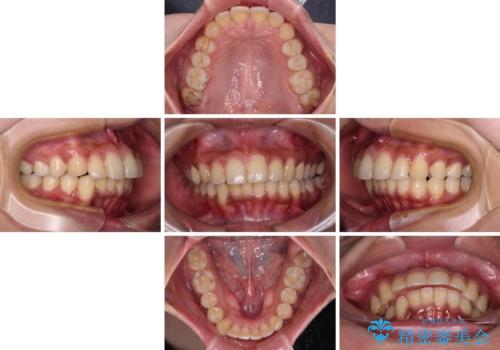

深い咬み合わせと前歯のデコボコ インビザラインによる矯正治療

治療途中では、左右ともに奥歯が咬みにくい状態が続き、問題なく噛めるようになるまでに長期間を要しました。

一方で、デコボコや下顎の前歯が隠れてしまうほどの深い咬み合わせはしっかりと改善されました。